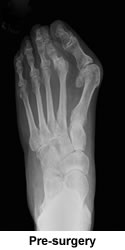

I recently read this passage in the novel Blue Shoe by Anne Lamont. Fortunately I hadn't read it before my surgery as it would have driven me even further into the shame, embarrassment, and disgust that I felt towards my own disfigured, ugly feet. When I did read it a few weeks ago, I silently thanked God for finding me Dr. Leavitt, rejoicing at the transformation he so skillfully brought about. I thought of my mother's equally deformed feet and wished that she, too, could have experienced the same reconstruction. There is no question that bunions are hereditary and if not corrected, can lead to far more serious problems.

As a child, my feet were the focus of much parental attention; my mother being convinced that well-fitting sturdy shoes would protect me from the same unfortunate deformities she suffered from. As an adult, I was constantly admonished that the pretty, stylish shoes I indulged in would ruin my feet. Whether caused by my genes or the shoes, my feet eventually were ruined, becoming increasingly so during a two year period after I retired; ironically, when I was no longer on my feet all day nor wearing pretty shoes. In fact, the only shoes I could wear were sneakers, which eliminated any dressing up for social events. Travel was also out of the question as walking was too painful.

After two previous surgeries for a bunion and a hammer toe, both of which left my feet in even worse shape, I was leery of risking any more. However, as my feet continued to fall apart and the pain worsened, I knew that something further must be done. I had heard good things about New England Baptist, but still somewhat dubious, I took the plunge and called the hospital for a referral to their best orthopedic foot surgeon. Without hesitation they recommended Dr. Leavitt. Not until after checking his web site did I make the appointment for a consultation. He was very thorough in his explanation of what he might do to correct my problems and answered my many questions about the surgery, the time I would spend in recovery, and how I might manage the eight weeks of being non-weight bearing.